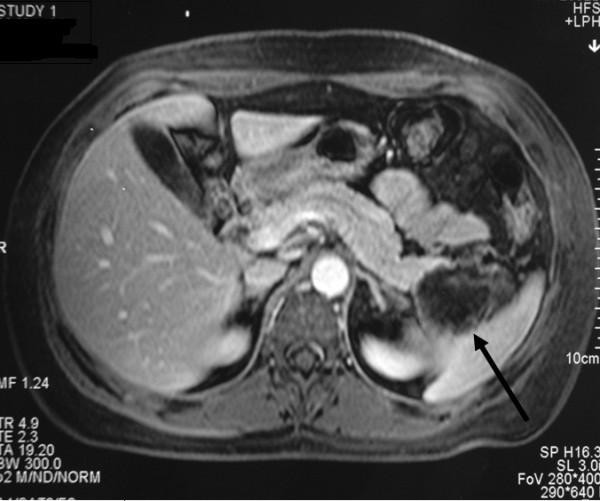

We report the case of a 55-year-old Greek woman with a solid pseudopapillary tumor of the tail of the pancreas. She underwent a laparoscopic distal pancreatectomy and splenectomy. The histopathologic examination finally revealed a cystic-solid pseudopapillary neoplasm of the pancreas. Solid pseudopapillary tumors of the pancreas are rare and affect predominantly young women. These tumors are of unclear pathogenesis and low malignancy, and surgical resection offers an excellent chance for long-term survival.

我们报告一例55岁希腊女性患者,患有胰腺尾部实性假乳头状肿瘤。她接受了腹腔镜远端胰腺切除术和脾切除术。组织病理学检查最终显示为胰腺囊实性假乳头状肿瘤。胰腺实性假乳头状肿瘤较为罕见,主要影响年轻女性。这些肿瘤的发病机制尚不清楚,恶性程度较低,手术切除为长期生存提供了绝佳机会。